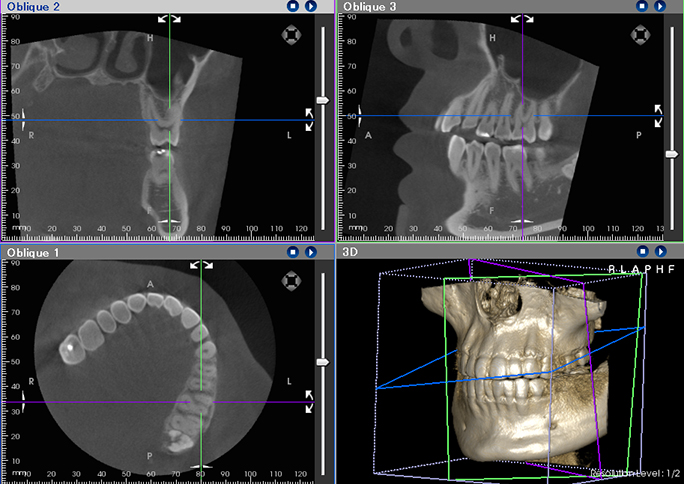

360度全週から撮影したデータでは、複数のデータ解析表示が可能であるとともに、スライスされる位置や角度を変えることが可能となります。本当に必要な部分の必要な角度での断面を見ることができます。

硬い骨質部分、通常の骨質、組織といった情報までもCT撮影にて確認する事ができます。

診断を行う材料として、患者様からのお話、見た目からの判断、レントゲン画像を総合して判断していきます。従来の2次元のレントゲン画像だけではなく3次元のCT画像が加わることにより「痛みの原因」「歯の状態」「骨の状態」「病巣の広がり」などを3次元でより詳細に確認することができ、正確な診断を行い適切な治療計画の決定が可能となります。